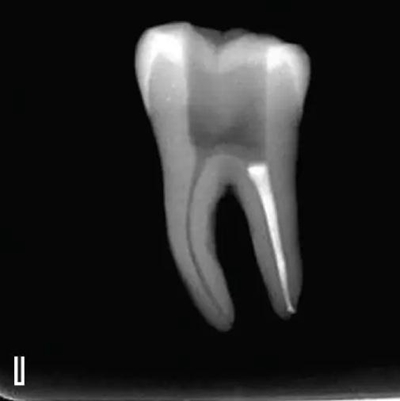

3、試尖

選擇非標(biāo)準(zhǔn)牙膠尖(如0.04、0.06 錐度牙膠尖)作為主尖,型號一般與根管預(yù)備最大號的器械型號一致,能到達(dá)距根尖0.5~1 mm 處,主尖尖段與根管壁緊密接觸。拍試尖X 線片進(jìn)行確認(rèn)(圖3)。

圖3 試尖,A.試主尖 B.拍試尖X片